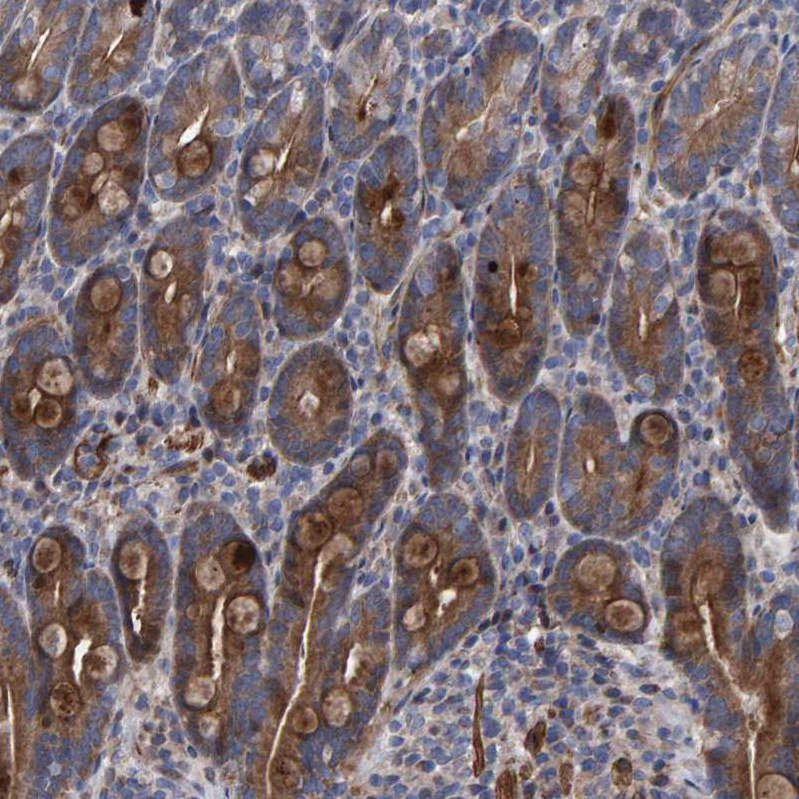

Immunohistochemical staining of human lung shows strong cytoplasmic positivity in macrophages.